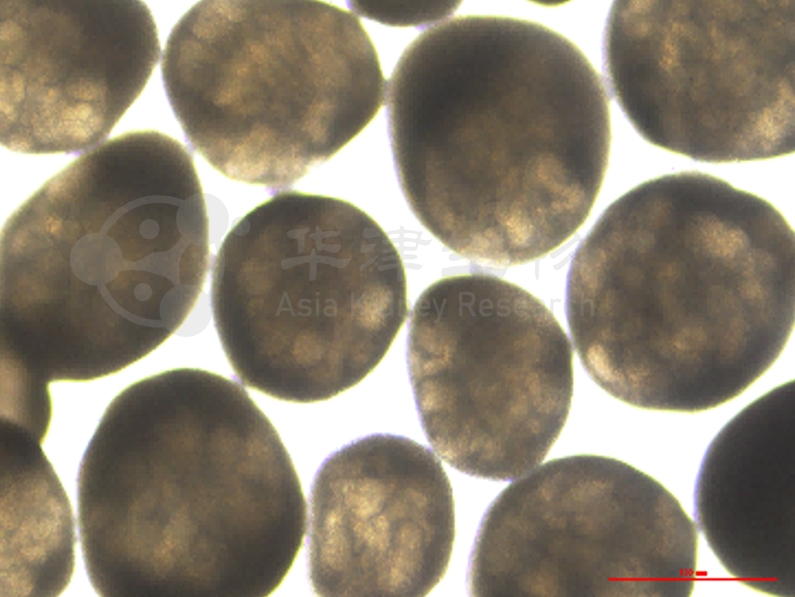

图1. 华津Kidnioid®技术平台的人源肾脏类器官

基于自主开发的Kidnioid®技术平台

• 具有肾小管,肾小球(足细胞),血管样等结构的肾脏类器官,直观显示小核酸药物的递送分布

• 肾脏类器官的标准化生产流程及批间差异的稳定,确保结果的可重复性

• 数个小核酸肾脏递送药物的项目经验,支持差异化研发需求及个性化解决方案

以某siRNA项目为例,华津基于Kidnioid®技术平台,在短时间内完成了多个候选分子的沉默效率评估,最高沉默率接近90%,成功筛选出具有潜力的先导化合物。